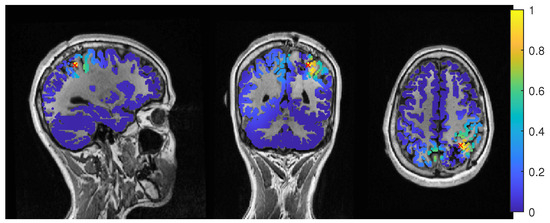

The beamformer and dipole scan localization results for patient 2 are shown in Figure 9. Here, the EEG (top row) and MEEG (bottom row) could localize into the resection, while MEG (middle row) could only localize close to the resection, but did not show much activity inside.

The event-related beamformer with the 6C head model localized into the resection volume with a high certainty for regularization parameters around 0.022. The localization with a parameter of 0.02 is shown in Figure 10. For higher values, both 6C and 3C head models localized 14 mm and 10 mm away, respectively, with strongly increasing certainty.

Without regularization ( α = 0 ), the average-based beamformers for both head models were 3 mm away from the resection, and an increasing distance to the resection volume can be observed with increasing regularization up to 8 mm and 13 mm for the 3C and 6C head models, respectively. The relative power was well above 1 for all parameters and both head models, thus localizing with certainty outside the resection.

The dipole scans for the 6C and 3C head models localized 29 mm and 31 mm away from the resection with gof of 99% and 98%, respectively. High gof was spread across the whole frontal lobe and was higher in the deeper parts. Both model’s relative power was high.

For MEG (Figure 9, middle row), the localization distances to the resection volume of the evaluated methods were generally higher than for the EEG, with the best localization still 7 mm away.

For the event-related beamformer, the 3C head model’s distance to the resection volume was 26 mm for the whole parameter range (bf-evt-3C in Figure 9, middle left subfigure). Its relative power was around 2.8 for all parameters, which is outside the shown range (middle right subfigure). The 6C head model (bf-evt-6C) showed an overall lower distance to the resection volume of 20 mm up to a regularization parameter of 0.034 and 18 mm above that value. Its relative power showed slightly more fluctuation, but gave high certainty to a localization outside the resection volume for all parameters. The average-based beamformer in the 6C head model (bf-avg-6C in Figure 9, middle left subfigure) had a distance to the resection volume of 8 mm (regularization parameters between 0.008 and 0.08) and 15 mm (above 0.08), while it was higher at lowest regularization. The 3C head model (bf-avg-3C) performed similarly, with 7 to 8 mm distance to the resection volume for a regularization above 0.026. Lower or no regularization led to very high distance values.

The dipole scans for the 6C and 3C head models localized in 31 mm and 37 mm distance to the resection volume with low gofs of 55% and 54%, respectively. With a relative power of 1.4, both dipoles showed certainty in their localization outside the resection.

The results of the combined MEG and EEG source analysis (Figure 9, bottom row) swayed between the EEG and MEG results, improving but also worsening some localizations.

The 6C event-related beamformer’s (bf-evt-6C) results show a similar behavior for MEEG as for the EEG. For low regularization up to a parameter of 0.048, the distance to the resection volume was 3 mm. For higher parameters, the distance jumped to 24 mm, with a fast increase in certainty. The 3C model showed similar results, although it could localize inside the resection for a range of parameters and the increase in its distance only happened at a higher regularization parameter of 0.09.

The MEEG average-based beamformer for both head models (bf-avg-6C and bf-avg-3C) showed a comparable performance as for single modality EEG and MEG. For both head models, distances to the resection volume decreased with increasing regularization strength and stabilized at a distance of 8 mm for regularization parameters above 0.03. Their relative power was almost identical and rather high.

In Figure 11, the MEEG average-based beamformer localization at 0.05 regularization strength is presented.

The performance of the MEEG dipole scans for the 3C head model (Figure 9, bottom row, dip-3C) followed the EEG with a distance of 31 mm and a gof of 79%. The 6C head model’s localization was improved in comparison to the single modalities, although its distance was still 21 mm with a gof of also 79%. For both head models, the dipole scan showed certainty in the localization outside the resection volume.